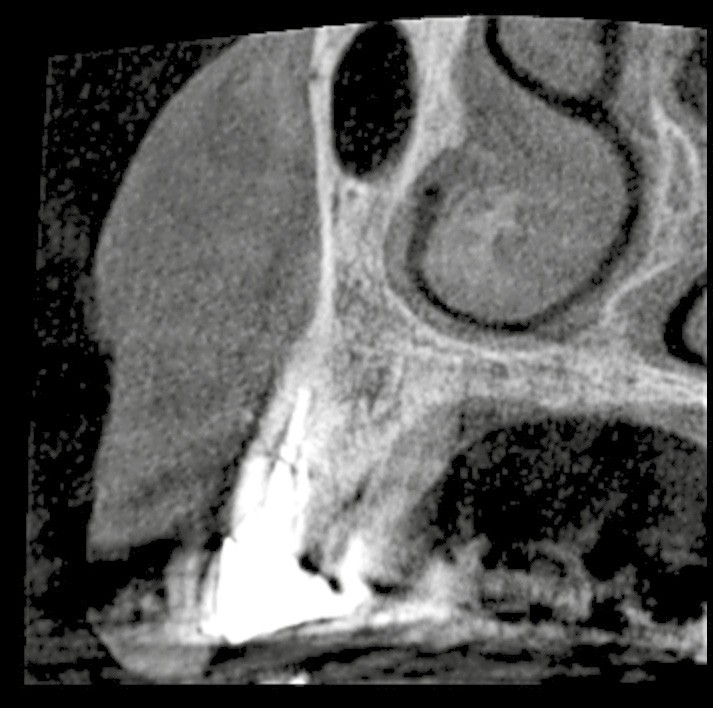

– l’alvéole de type II est caractérisée par l’absence d’altération du profil gingival mais par un déficit partiel de la table vestibulaire ;

– l’alvéole de type III présente une altération du profil gingival associée à un déficit osseux.